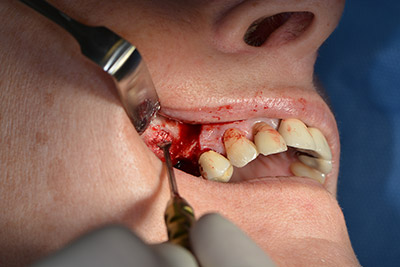

Quindi, abbiamo optato per il rialzo del pavimento sinusale con impianto simultaneo. Implantmed è preimpostato sulla prima posizione per quanto riguarda la fenestrazione buccale della parete del seno mascellare.

La fenestrazione è impostata su 35.000 rpm, mentre la mucosa nasale viene preparata in direzione craniale (da fig. 13 a 14).

Dunque, l'impianto viene posizionato e l'osso ricostruito. In questo caso, considerate le dimensioni della regione di accrescimento, i microframmenti dell'osso autologo (raccolti con un'apposita cannula di aspirazione in seguito alla perforazione dell'impianto 16 e della fenestrazione 14) vengono combinati con dei materiali di riempimento dell'osso.

Una membrana riassorbibile viene usata come barriera in direzione buccale per contenere l'accrescimento. Infine, vengono applicate suture resistenti alla saliva (da fig. 15 a 19).